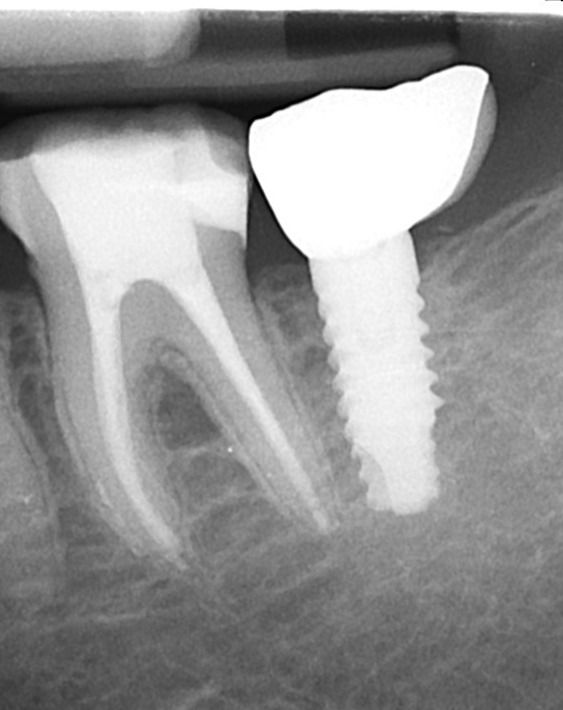

La morfologia convergente del collo Prama permette di recuperare la porzione di tessuto molle che con un impianto transmucoso tradizionale verrebbe occupata dal titanio del collo implantare. La convergenza di Prama fa sì che i volumi intorno alla porzione coronale dell’impianto vengano invece riempiti di coagulo e di importanti fattori di ricrescita, che si trasformano in tessuti molli spessi e funzionali.

L'ispessimento della gengiva che circonda il collo Prama rappresenta un beneficio indiscusso, soprattutto nei pazienti con biotipo più sottile, nei quali questo innovativo impianto apporta un ispessimento dei tessuti molli senza ricorrere a terapie rigenerative.

La stabilizzazione del connettivo, resa possibile dalla morfologia convergente e dalla microrigatura UTM, fa sì che tutto ciò che vi è al di sotto rimanga protetto e isolato da potenziali attacchi batterici, e che quindi l’osso si mantenga preservato in maniera efficace e a lungo, come ampiamente dimostrato dalla clinica.